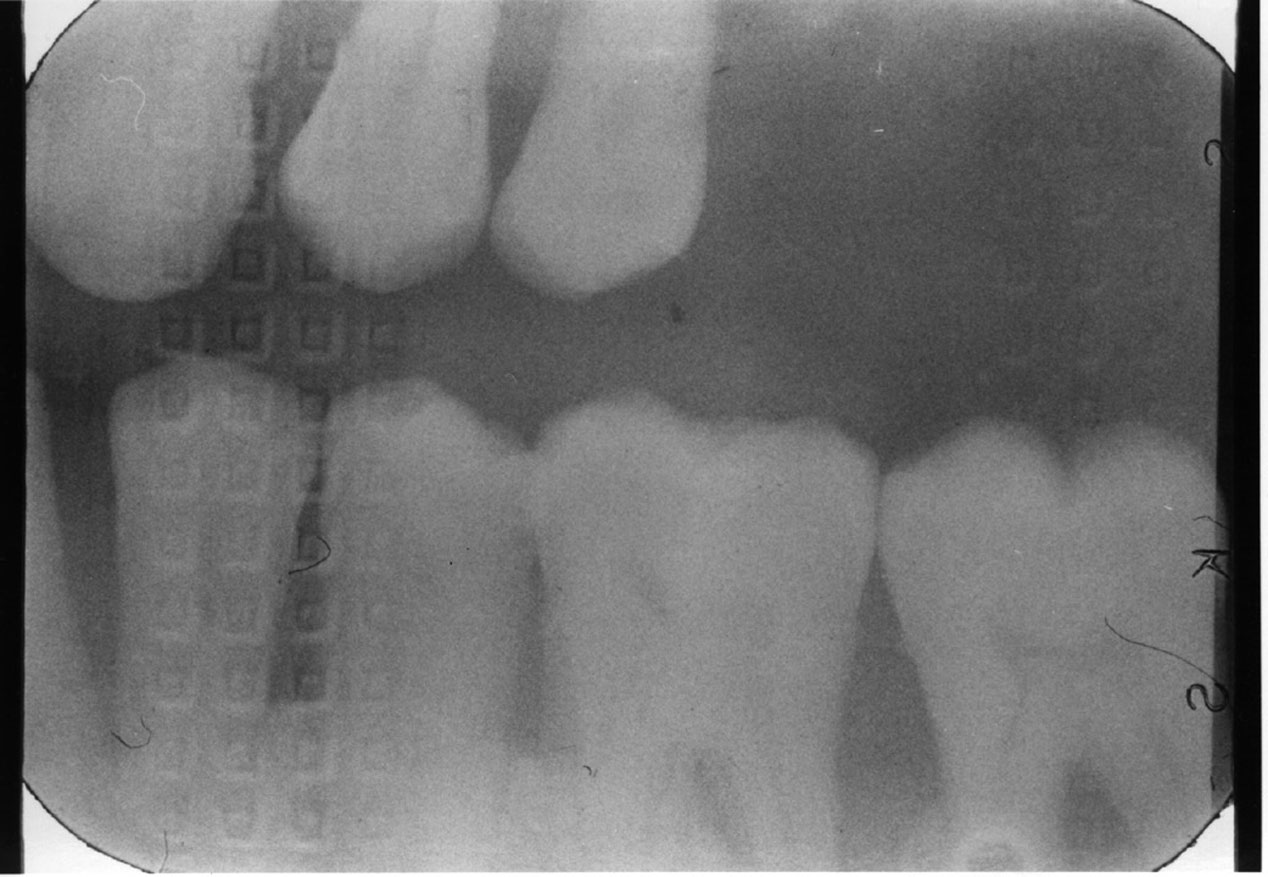

Double Exposure

Description: Double exposures occur when the same film is used for more than one exposure (Figure 1). This can occur if the operator confuses an exposed film with an unexposed film and places the packet into the patient’s mouth as if it were unused. Double exposures can also result from activating the exposure button twice.

Differential Diagnosis: The resulting film is dark because it has technically been overexposed, resulting in confusing, overlapped anatomic images.

Consequences: Retakes are almost always necessary because of the lost detail caused by anatomic superimpositions. Fortunately, double use of a packet usually occurs with the same patient in the chair; but if a previously exposed film from one patient were placed into the mouth of another, the operator would be running the risk of cross-contamination and transmitting disease between patients.

Remedy: After a film packet has been exposed the op­erator should place the film into a lead receptacle. Unexposed films and exposed films should never be kept in the same area.

Figure 1. Double exposure.

Figure 1